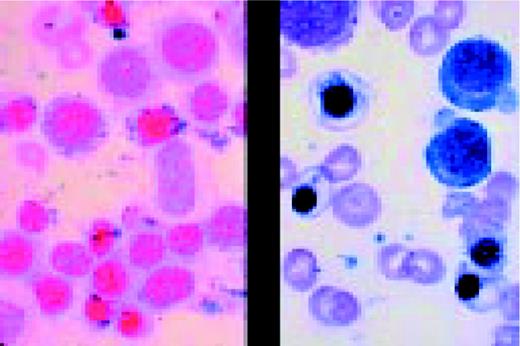

Slide L14

Prolymphocytic leukemia (PLL). This composite slide shows prolymphocytic leukemia (PLL) from two different patients. On the left is B cell PLL and on the right, T cell PLL. The B-PLL cells correspond to the classic description of Galton et al. (Br J Haematol 27:7, 1974): They are larger than CLL lymphocytes, have condensed chromatin, and have prominent large nucleoli. The T-PLL cells have a less conspicuous nucleolus, an irregular nuclear outline, and cytoplasmic blebs, as described by Matutes et al. (Blood 78:12, 1991). In many cases it may (FIX) be difficult to distinguish B-PLL from T-PLL cells on morphologic grounds alone, without performing additional immunophenotypic studies.FIG14